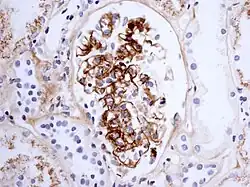

La maladie se caractérise par un dépôt d'immunoglobuline de type A1 dans les parois des vaisseaux et dans le tissu rénal (mésangium).